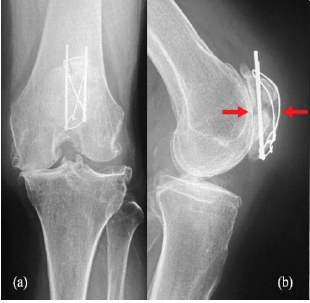

Simultaneous TKA and Revision of Post-ORIF Patellar Non-union with Bone Grafting: A Case Report

Hiroko Sakamoto , Masaki Nagashima , Ryo Sasaki , Kentaro Tanaka , Mitsuru Yagi

………………………………p.157-162